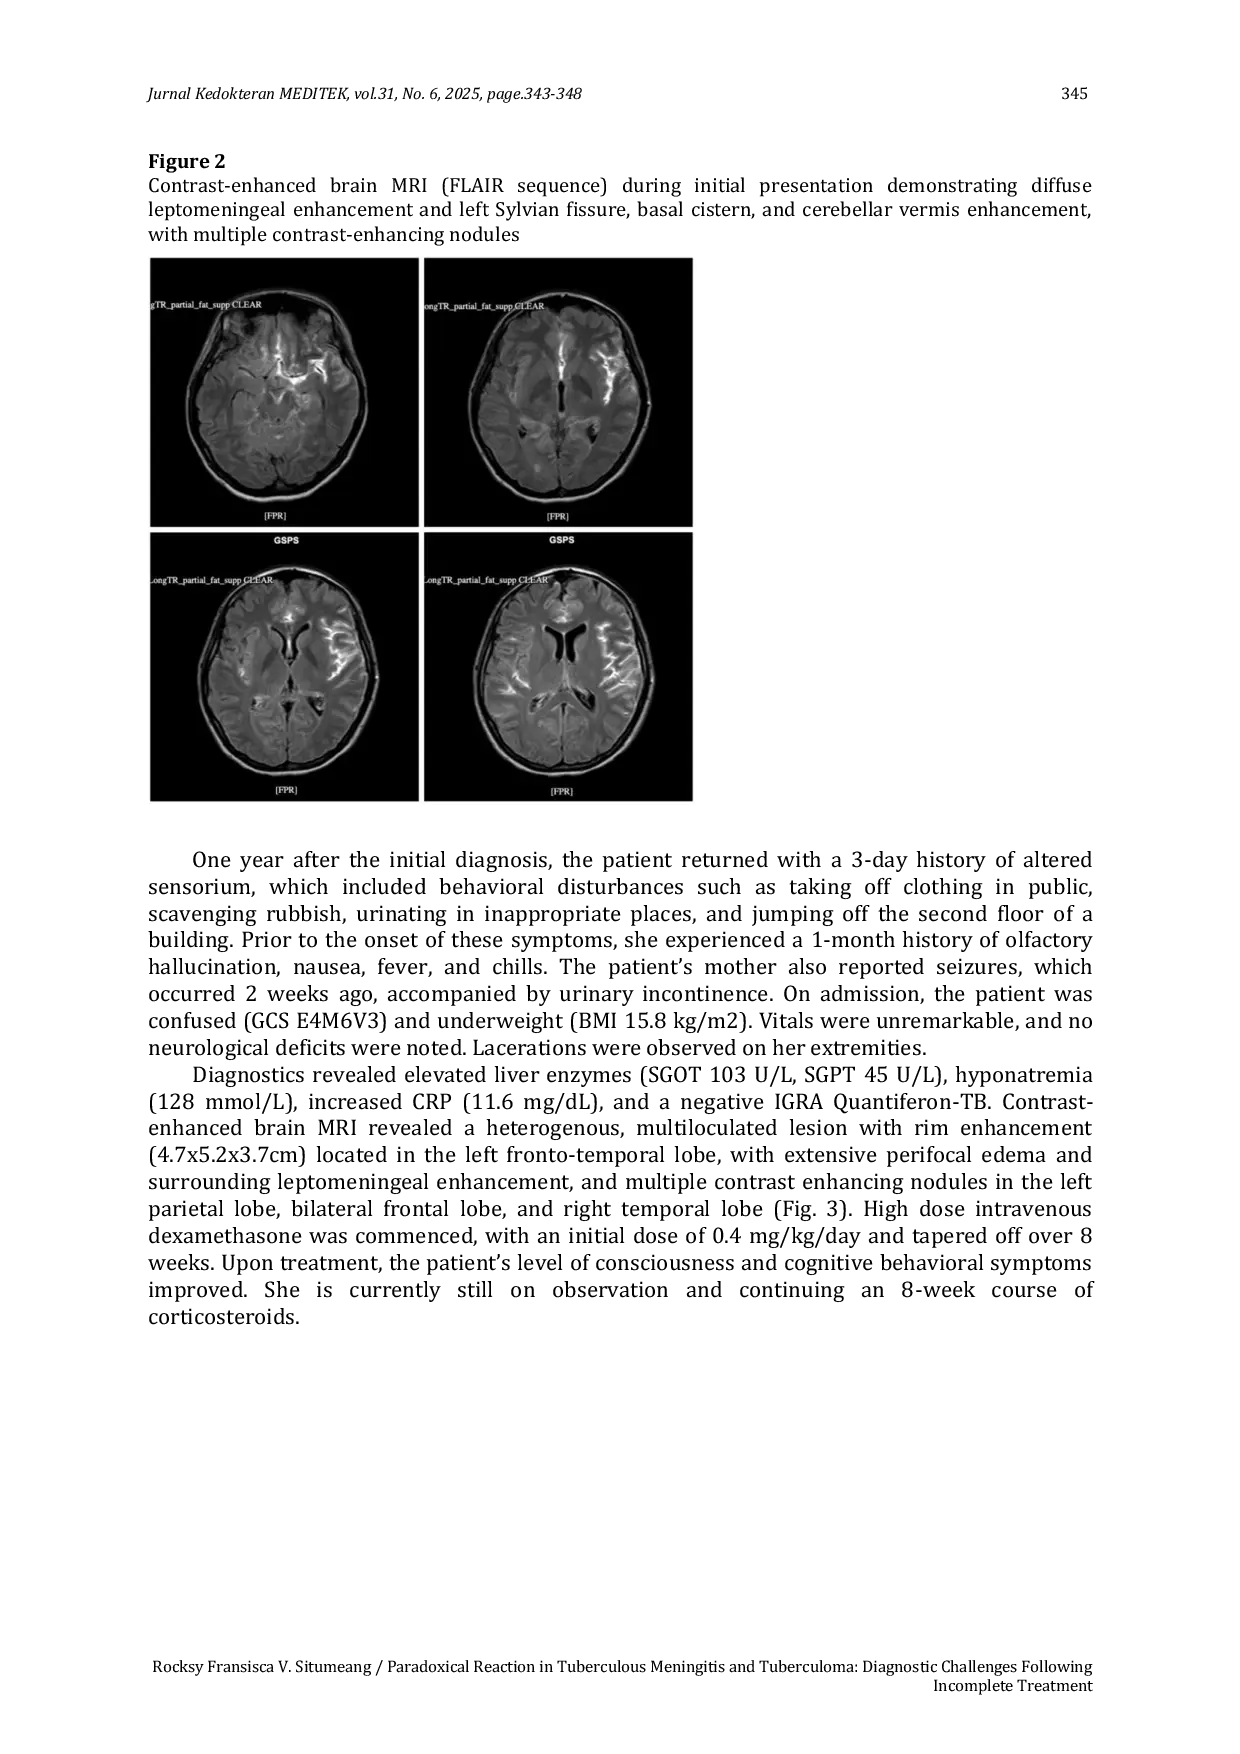

Jurnal Kedokteran MeditekJurnal Kedokteran MeditekReaksi paradoks pada tuberkulosis meningitis dan tuberkuloma menunjukkan tantangan diagnostik setelah pengobatan yang tidak lengkap. Studi ini menyoroti potensi terjadinya reaksi paradoks dalam konteks regimen pengobatan anti-tuberkulosis yang tidak selesai. Pasien berusia 20 tahun mengalami penurunan kesadaran dan perubahan perilaku setelah pengobatan yang tidak lengkap, dengan MRI menunjukkan lesi baru. Diagnosis reaksi paradoks ditegakkan dan pengobatan kortikosteroid intravena dilakukan, menghasilkan perbaikan klinis dan radiologis. Reaksi paradoks tetap menjadi tantangan diagnostik, sering kali disalahartikan sebagai relaps mikrobiologis, resistensi obat, atau kegagalan pengobatan. Hal ini muncul dari respons imun terhadap antigen mycobakterial, membedakannya dari relaps atau resistensi obat.